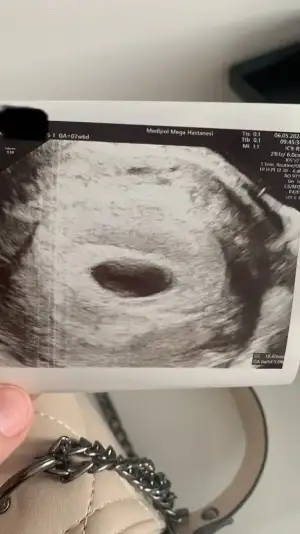

Ben 6.haftada hamile olduğumu öğrendim. Beta hcg 19.000 bindi. Hemen doktora gittik, keseyi gördük. 9 mmdi.

6+6 da kontrole gittim kese 25 mm olmuş. Hcg değerim de 37.000 olmuş. Ama bebek ve kalp atışı yok. Ultrasonda kese fotoğraftaki gibi gorunuyor.

Kesede ufak bir şey gorunuyor ama doktor bişey demedi. Haftaya tekrar bakacağız dedi. Sizce burada bir şey var mı? Benimle benzer durumu yaşayıp bebeği sonra gören var mı? Boş gebelik olmasından dolayı endişe duydum. Hcg değerlerim normal mi?